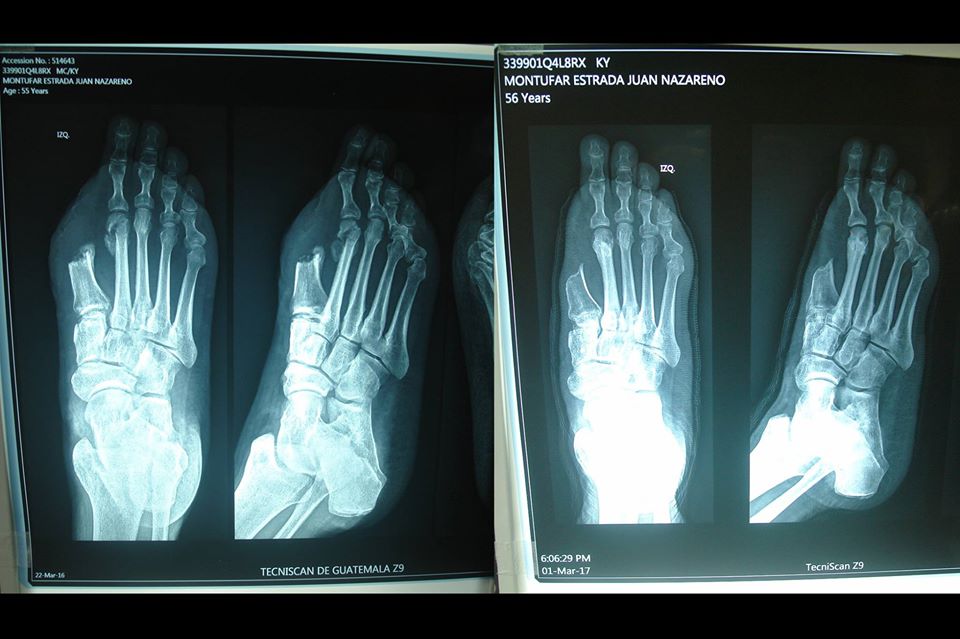

En las fotografías se observa, la zona del dedo amputado, el hueso del 2o metatarsiano fracturado en la cabeza, por osteomielitis y la silueta del pie hinchado… en segunda radiografía, un año después la silueta del pie es normal, y el hueso se ha restaurado completamente. Osteomielitis resuelta…